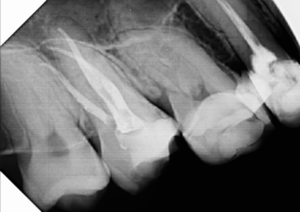

Alguns trabalhos